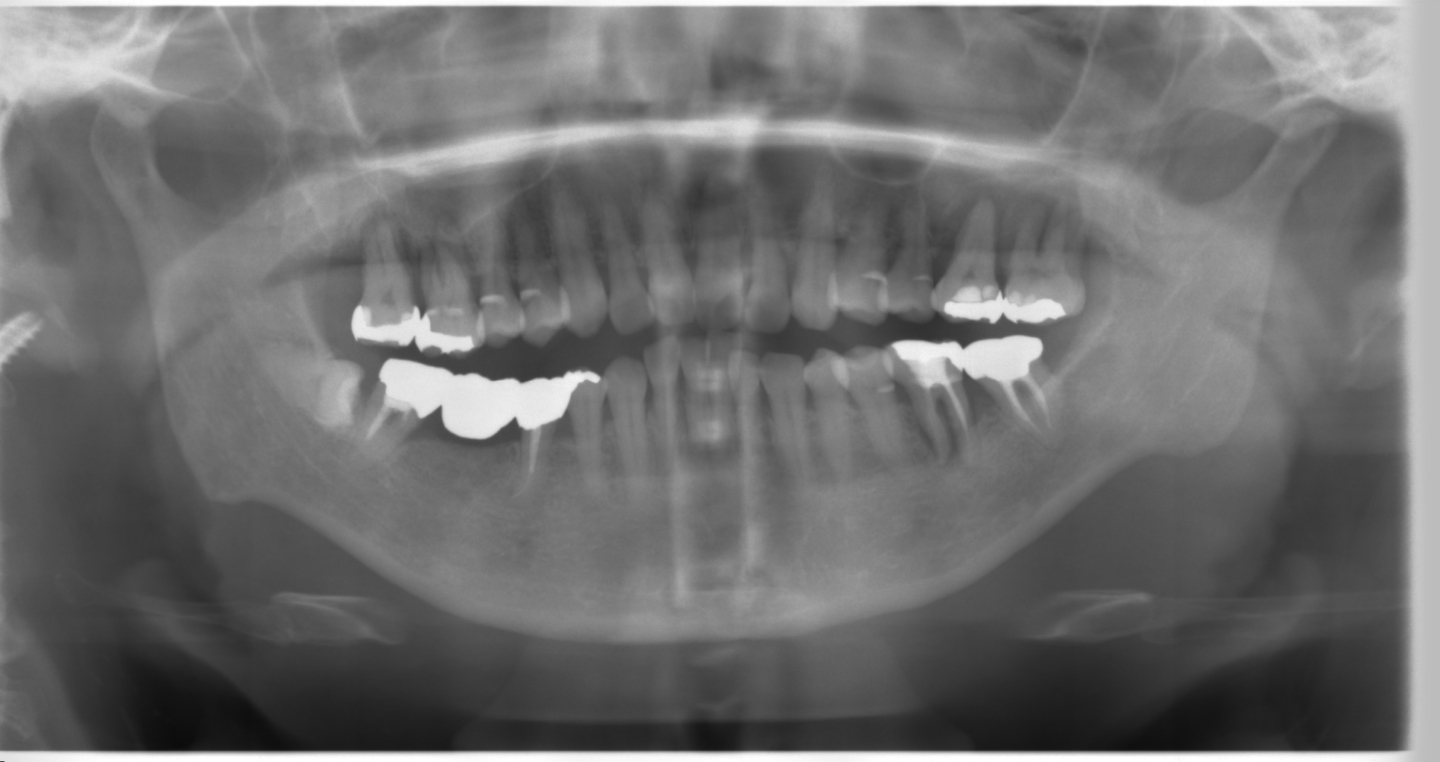

まずはこちら、写真では向かって左下に親知らず(水平埋伏智歯)があるのがわかります。

実際の口腔内では右下の8番目の歯になります。

ここの病院では親知らず以外の歯の治療が優先されていました。

主に親知らず以外の抜歯がメインです。

左上67番の大臼歯2本が抜歯となりました。

加えて右上67番の大臼歯と左下6番の第一大臼歯が抜歯となりました。

その後、入れ歯やブリッジを検討されたそうですが口腔内に馴染まず放置してしまったそうです。

結果として左下7番の第二大臼歯は近心に傾斜し、すでに補綴処置が困難な状態になってしまいました。

と同時に右下8番の親知らずから右下7番の第二大臼歯にかけて骨が急速に溶けているのがわかりますでしょうか?

元々ブリッジ治療の支えになっていた右下7番と埋まっていた親知らずの間に歯周ポケットがあり、これが4mmから5mmに、5mmから6mmに年々深くなり、最終的に親知らずと手前の歯の間の溝が深くなった結果、右下の歯が全体的に悪くなってしまった症例です。

もちろん、右下の親知らずだけが原因とは言い切れませんがこの親知らずが無かったら右下のブリッジの支台歯と右下のブリッジはもっと寿命が長かったかもしれません。